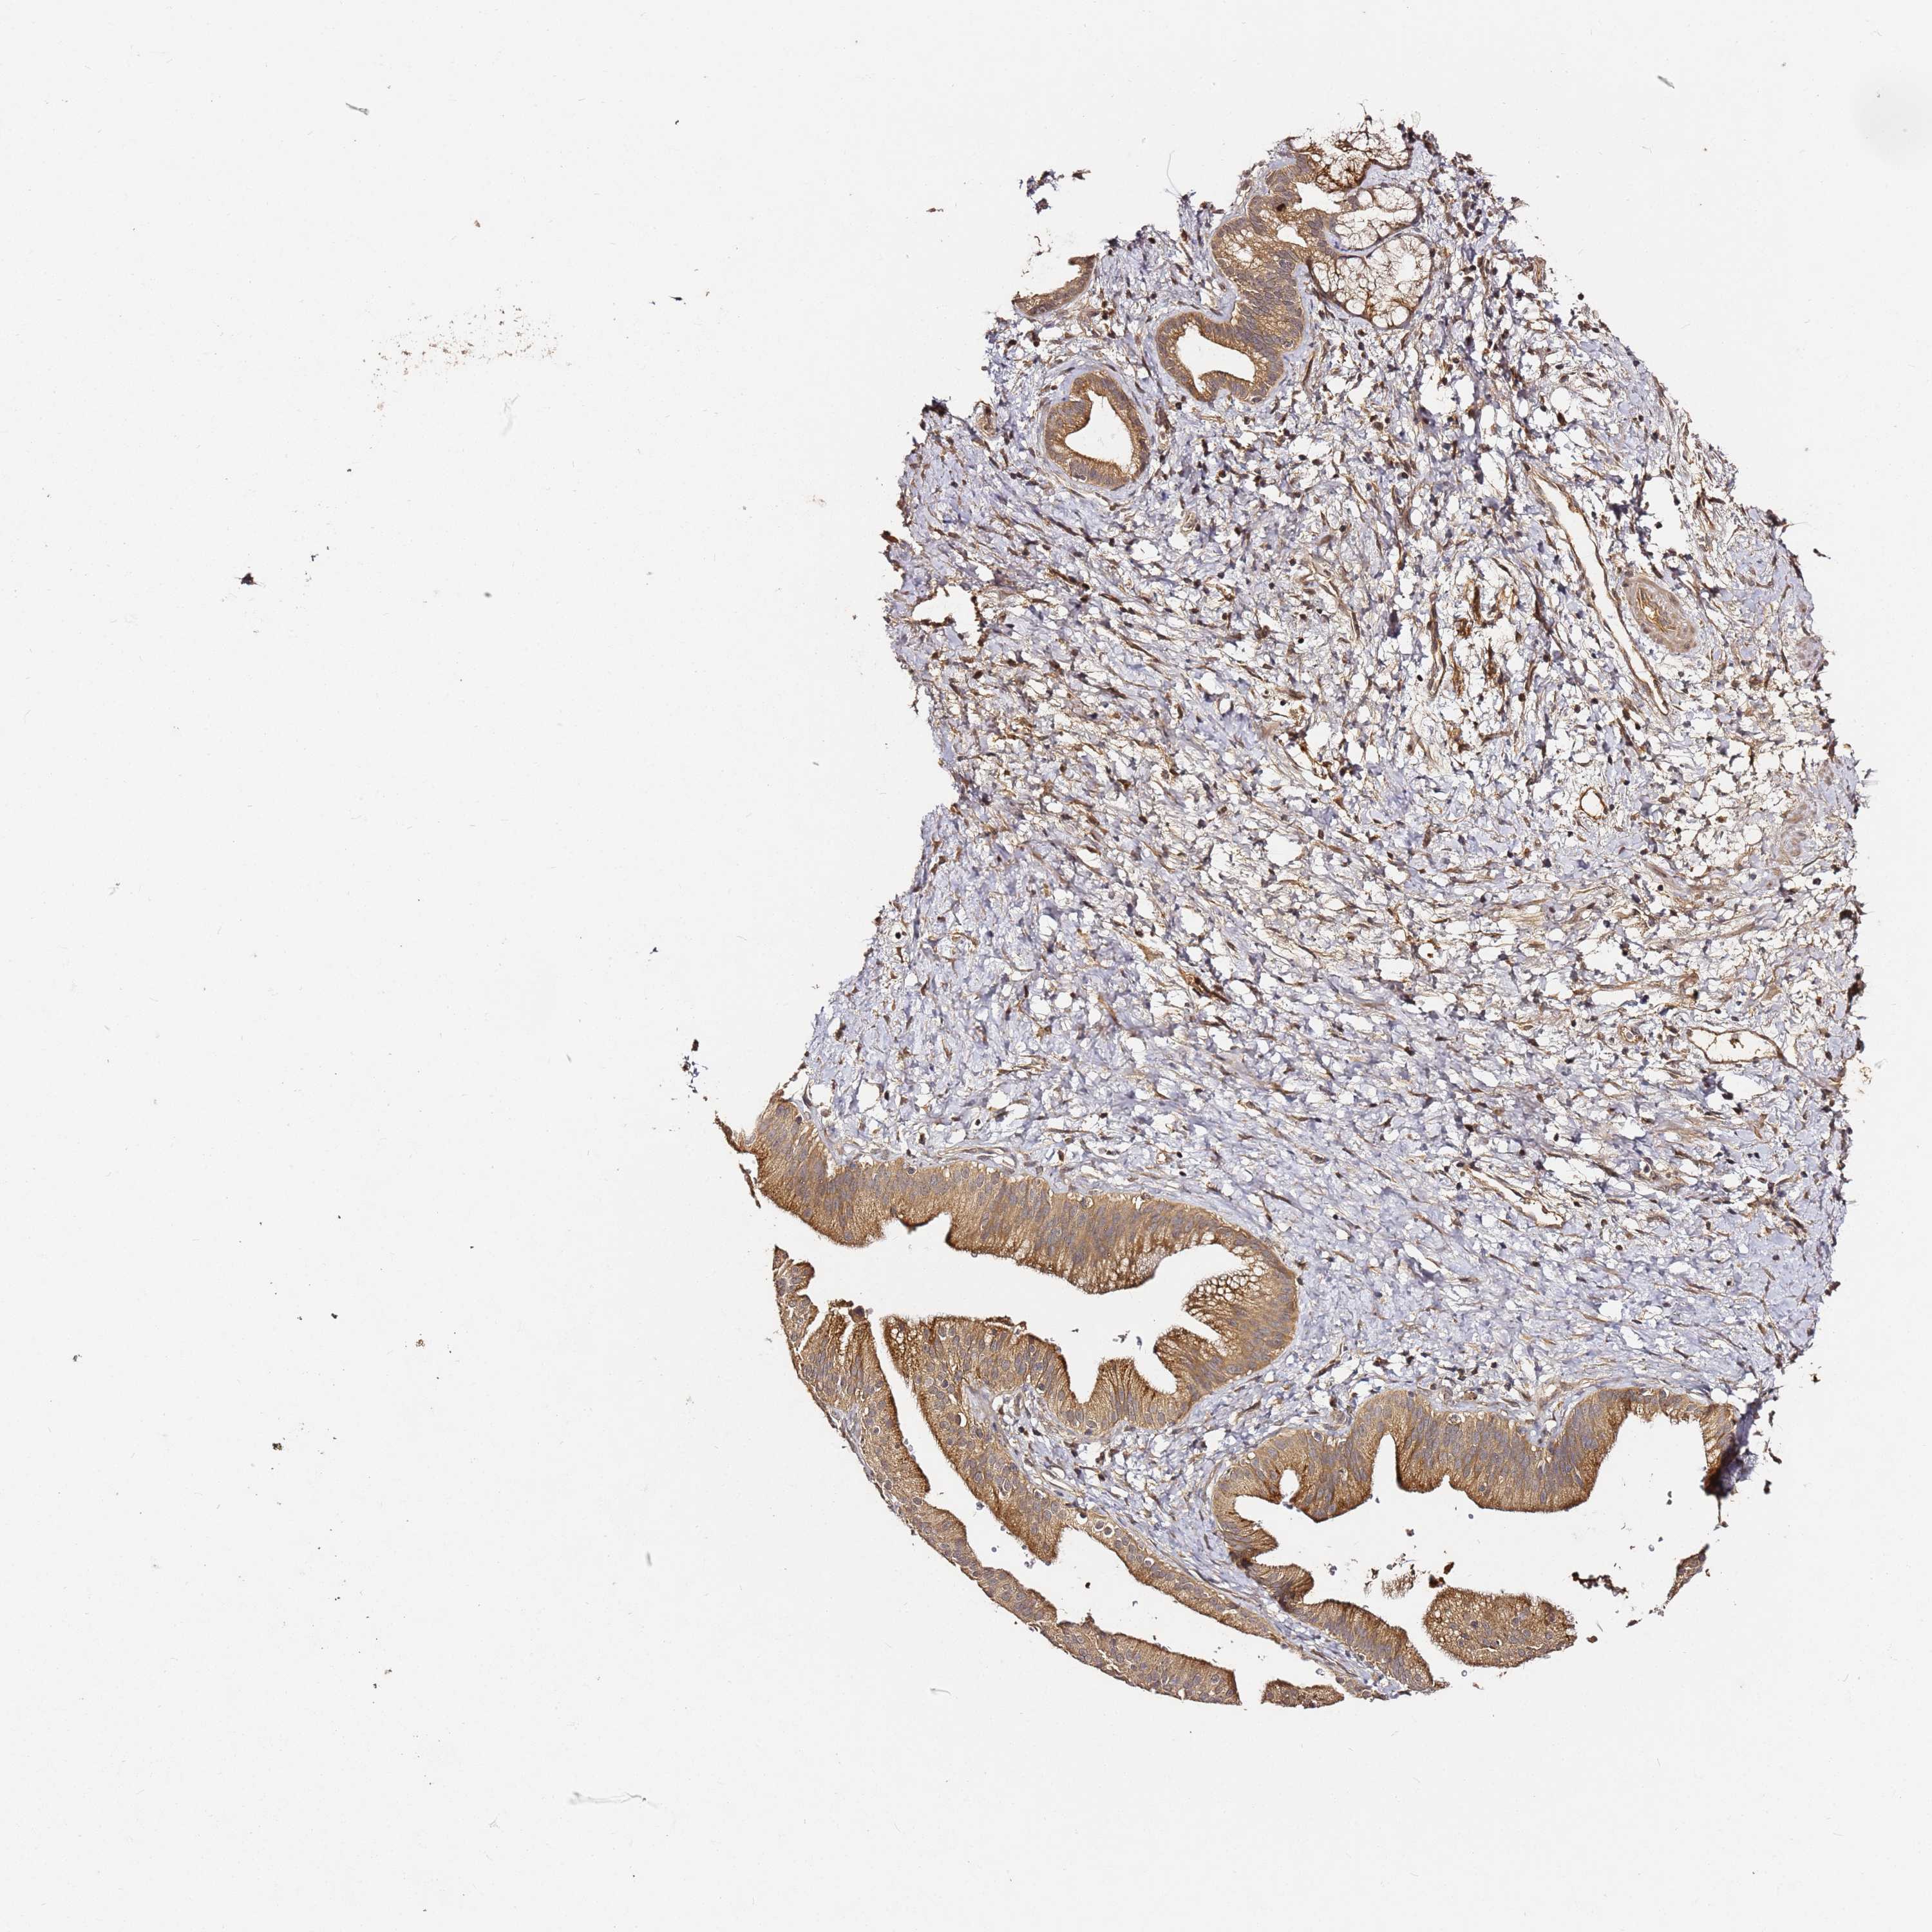

PANCREATIC CANCER - Protein expressioni

A mouse-over function shows sample information and annotation data. Click on an image to view it in a full screen mode. Samples can be filtered based on level of antibody staining by selecting one or several of the following categories: high, medium, low and not detected. The assay and annotation is described here.

Note that samples used for immunohistochemistry by the Human Protein Atlas do not correspond to samples in the TCGA dataset.

Antibody stainingi

Antibody staining in the annotated cell types in the current human tissue is reported as not detected, low, medium, or high, based on conventional immunohistochemistry profiling in selected tissues. This score is based on the combination of the staining intensity and fraction of stained cells.

Each image is clickable and will lead to virtual microscopy that enables deeper exploration of all samples and also displays staining intensity scores, fraction scores and subcellular localization as well as patient and tissue information for each sample.

Antibody HPA046804

Staining

High

Medium

Low

Not detected

Intensity

Strong

Moderate

Weak

Negative

Quantity

>75%

75%-25%

<25%

None

Location

Nuclear

Cytoplasmic/membranous

Cytoplasmic/membranous,nuclear

Adenocarcinoma, NOS